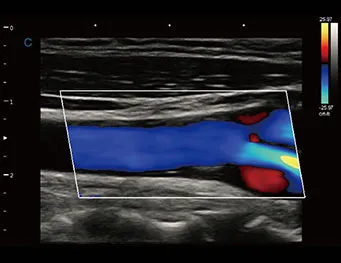

Zoom C HD

Haga zoom en la información de color, siga siendo la alta resolución.

Importante para la detección de información de sangre de vasos pequeños, especialmente para el diagnóstico de corazón fetal.